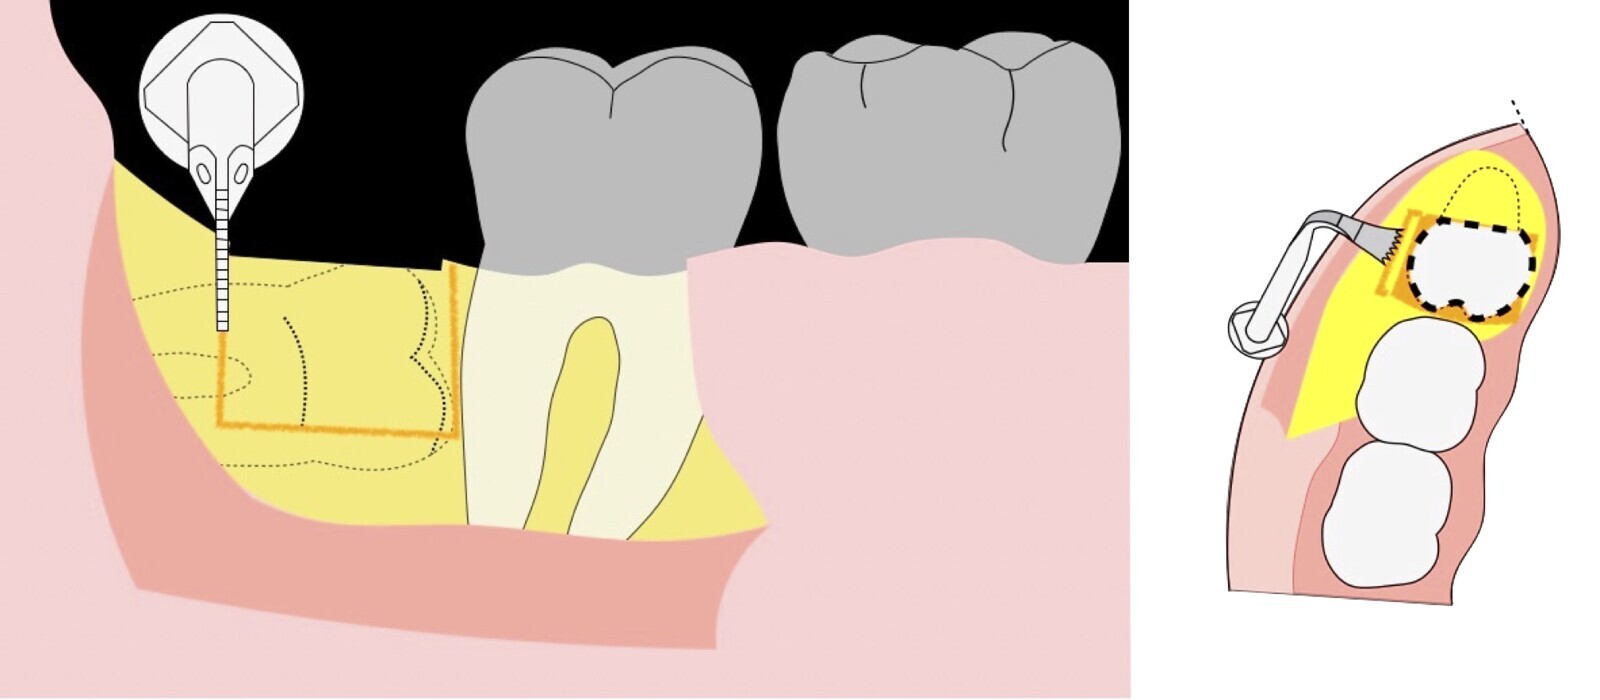

Figura 16. Cauterización con inserto de punta de coagulación del electro bisturí (a). Elevación del colgajo (b). Osteotomía con el inserto plano de corte de punta aserrada del piezoeléctrico (c).

Figura 17. Osteotomía con el inserto plano de corte de punta aserrada del piezoeléctrico (a, b). Demarcarción de los límites de la ostectomía del fragmento óseo (c).

Figura 18. Finalización de la osteotomía del primer fragmento óseo con inserto plano de corte de punta aserrada del piezoeléctrico (a, b, c).

Figura 19. Retiro del primer fragmento óseo (a, b). Extirpación del segundo bloque óseo con el inserto plano de corte de punta aserrada (c).

Figura 20. Retirada del segundo fragmento óseo (a). Ampliación de la ventana ósea con el inserto plano de corte de punta aserrada (b).